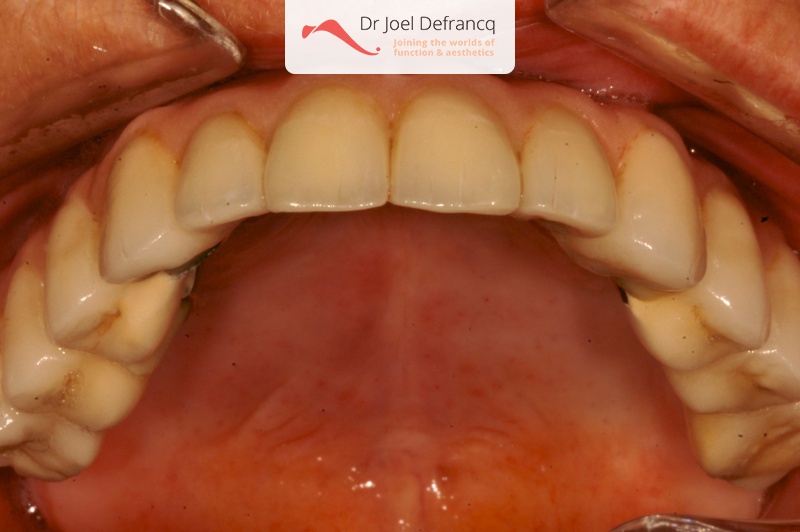

Dentale diagnose

- Open beet

Behandeling tandheelkundige implantaten

- Vaste tanden op implantaten (bovenkaak)